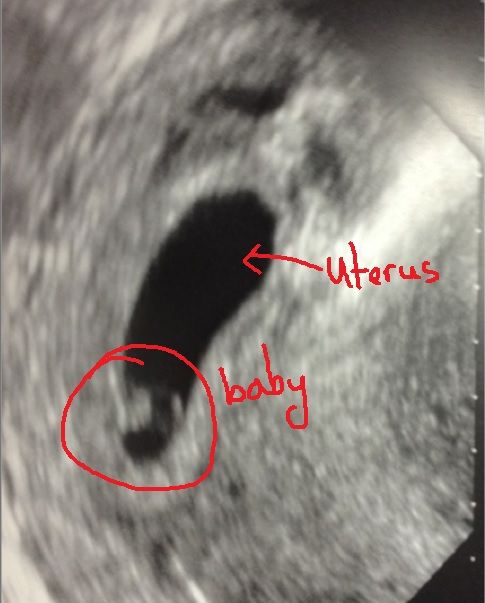

すいません、よく解んないんですが・・・。

ほい。

かなり初期の超音波画像でしょ。

5週目位か?

メチャクチャ小さいから、胎児を見つけづらいんだよね。

それが更に35週経過すれば、立派な赤ちゃんに育つんだよなあ・・・。

そ。この時は6週目。

今は14週でとっても大きいし、悪魔みたいな見てくれじゃないわよw

赤ちゃん参考画像。

自分のはこんな感じだったよ。